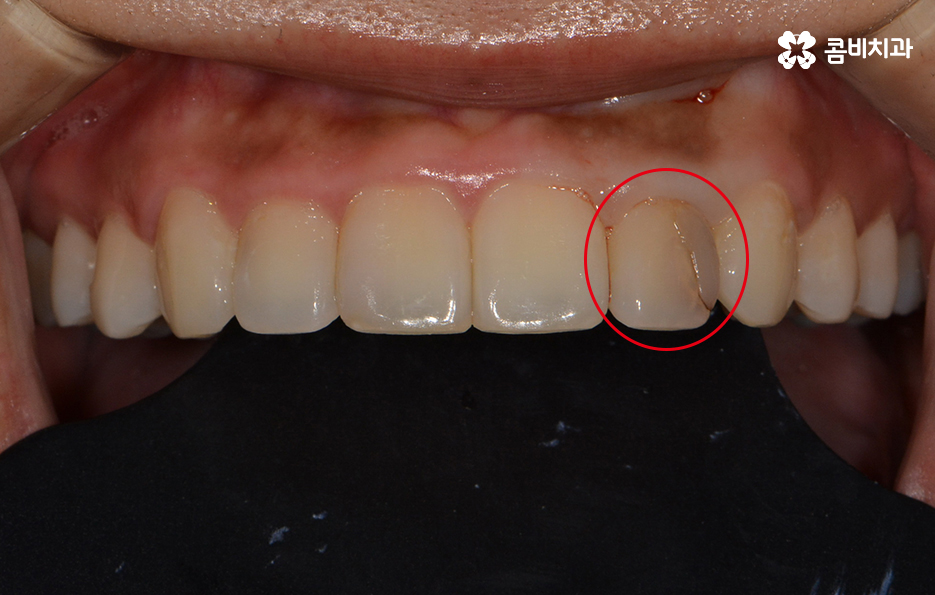

위 환자분의 경우 기존에 타 치과에서 치료받으셨던

라미네이트가 깨져서 내원하셨습니다.

앞니 충치치료 후 레진이나 라미네이트가 깨지는 사례가

종종 있는데 치료 후에는 평상시 생활 습관에 있어서

주의가 필요하며 이 악물기와 같은 습관이 있으신 경우

검사를 통해 개선 방안과 원인을 찾아보는 게 좋습니다.

또한 치아의 법랑질이 살짝 깨지거나 치료를 이미 했던

부위가 깨진 경우에 당장 이가 시리거나 아프지 않더라도

치과에 가서 바로 치료를 받는 것이 중요합니다.